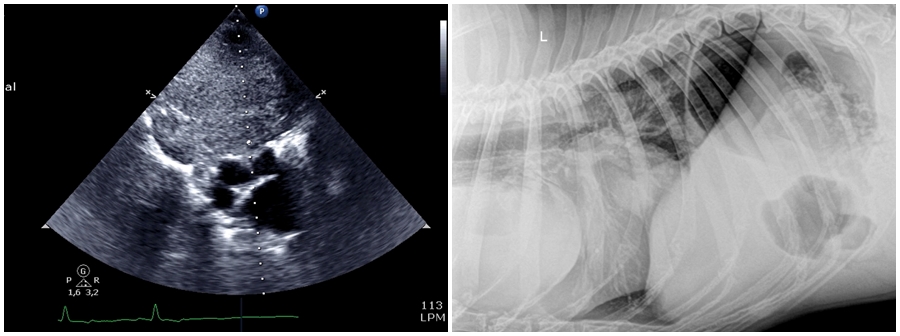

Cuerpo extraño/piedra

Paciente que acude con vómitos que no cesan con tratamiento médico, pérdida de peso y…